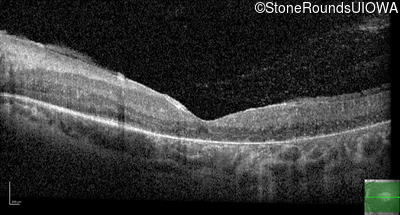

Optical Coherence Tomography - Left - 20/80 -1

Exemplar / OCT Stack

OCT Stack